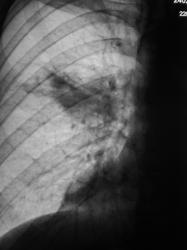

3.VICh_.JPG

Пока на данном этапе тянет на "прикорневую пневмонию с вовлечением S6", может и туберкулез выплыть. Нужны анализы и время.

О туберкулёзе тоже думали, и с учетом локализации, и с участившимися случаями "ВИЧ + туберкулёз".

а на томограммах вовсе узлом смотрится... и сочетание "ВИЧ+опухоль" тоже не редкое...